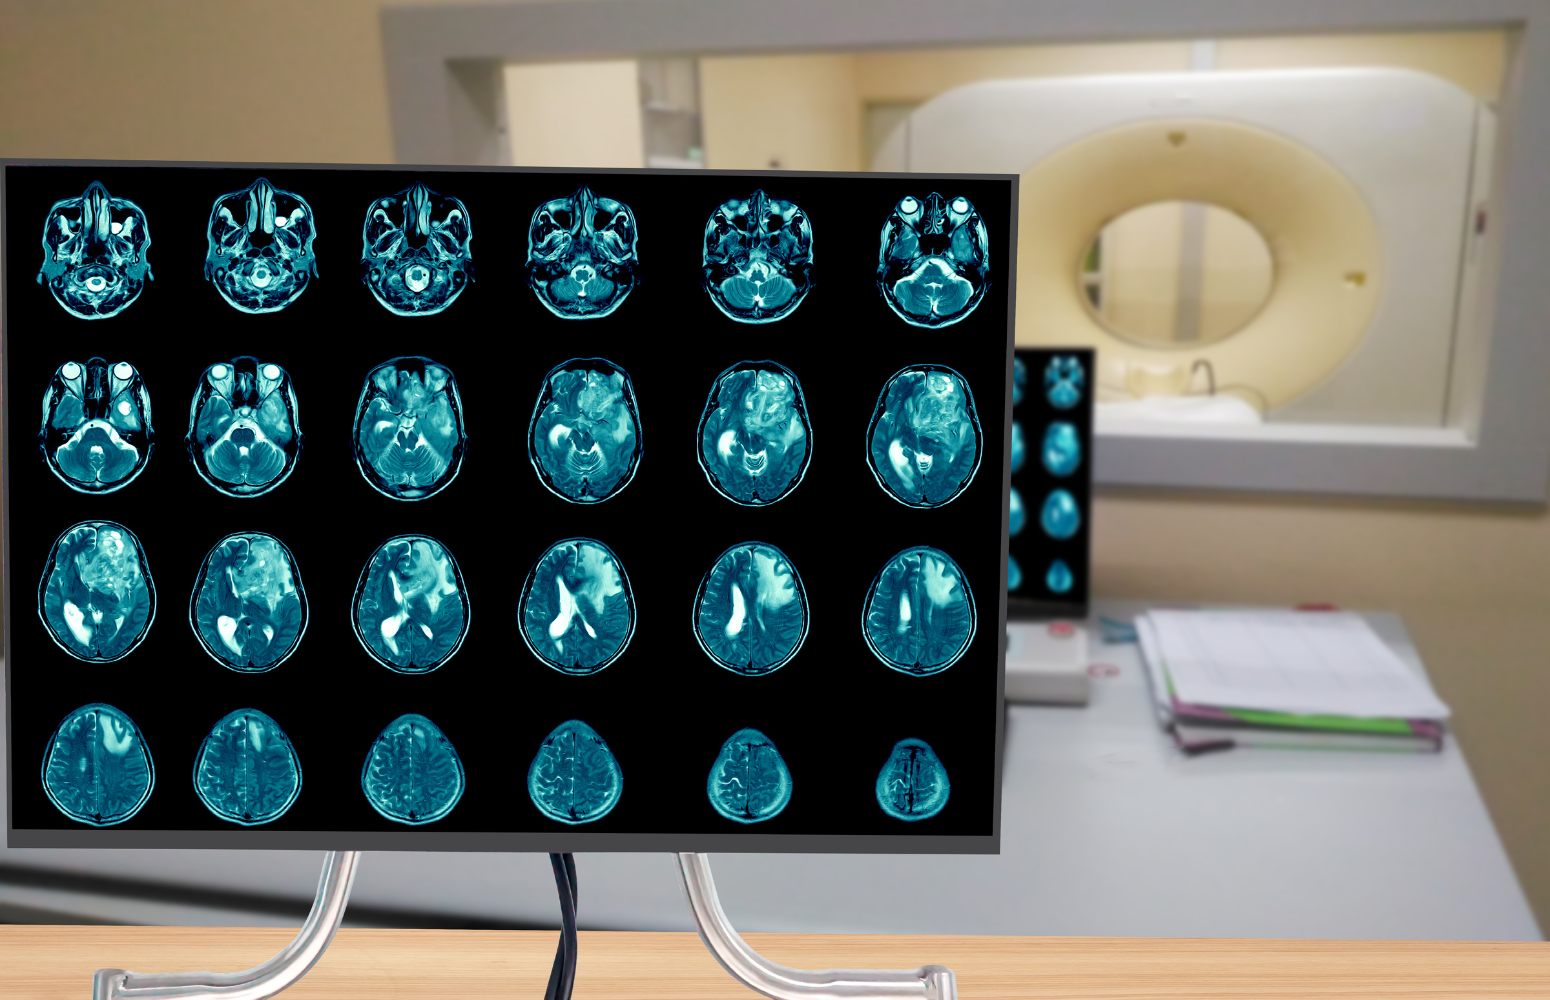

Read MoreUnderstanding Glioblastoma: Challenges, Treatment Advances, and the Road Ahead

Home At Healius Cancer & Hematology Clinics, we believe that every patient...